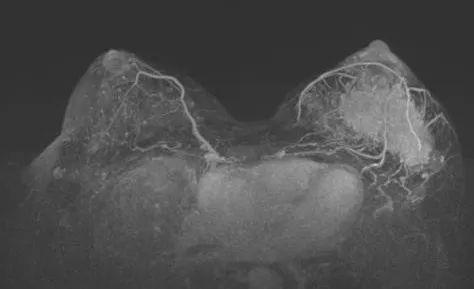

图片

图7. 左图为治疗前,右图为治疗6周期后

治疗6个周期后,乳腺增强MRI显示靶病灶明显缩小,临床疗效评估为PR;腋窝靶病灶消失,临床疗效评估为CR。